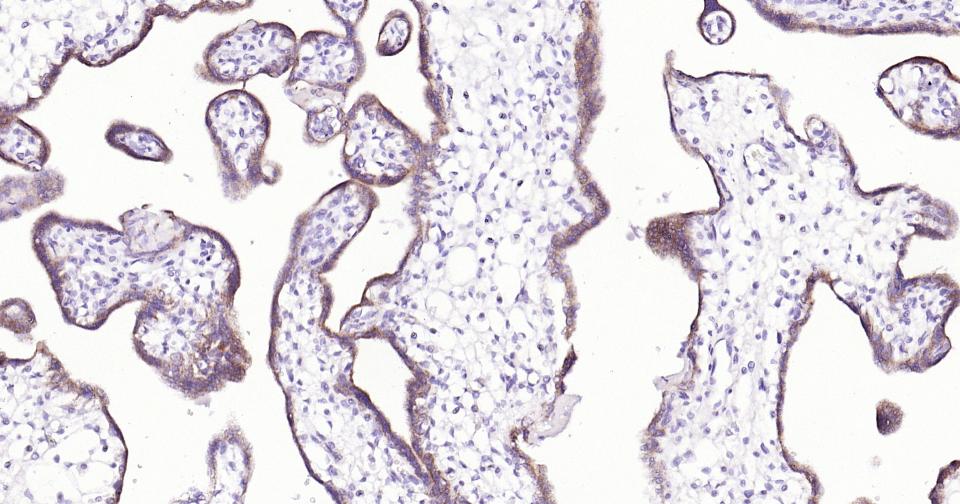

Paraformaldehyde-fixed, paraffin embedded Human Placenta; Antigen retrieval by boiling in sodium citrate buffer (pH6.0) for 15 min; Antibody incubation with LRP2 Monoclonal Antibody, Unconjugated(bsm-42103R) at 1:200 overnight at 4°C, followed by conjugation to the SP Kit (Rabbit, SP-0023)and DAB (C-0010) staining.